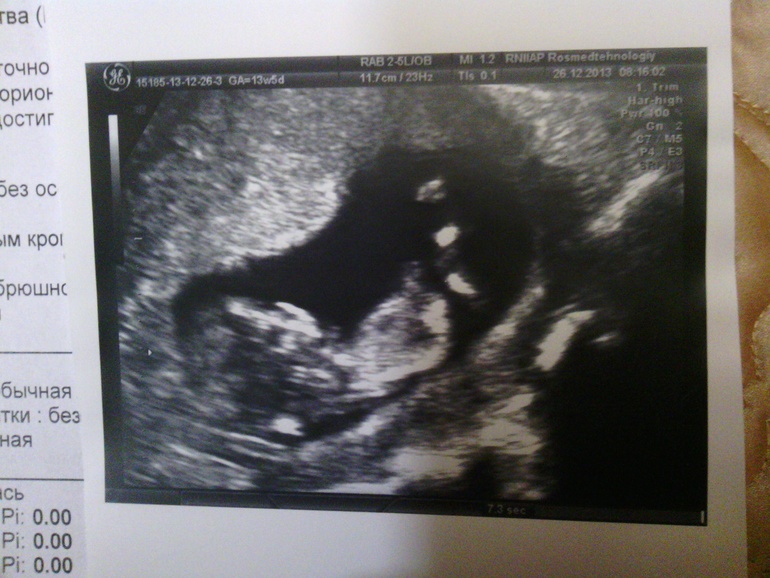

Девочки,срок 12-13 недель...как вы думаете,кто будет? Фоточки малышика ниже)

девочка 100 процентов. бугорок параллельно позвоночнику.если б мальчик то 30 градусов наклон был бы

какая деушка,видно же..кое что))причем если не на первой-там размыто-то четко се на 2 по-моему видно картинке)))